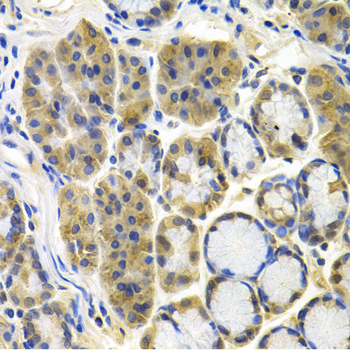

Immunohistochemistry of paraffin-embedded human colon carcinoma using APBB1 antibody at dilution of 1:100 (x400 lens).